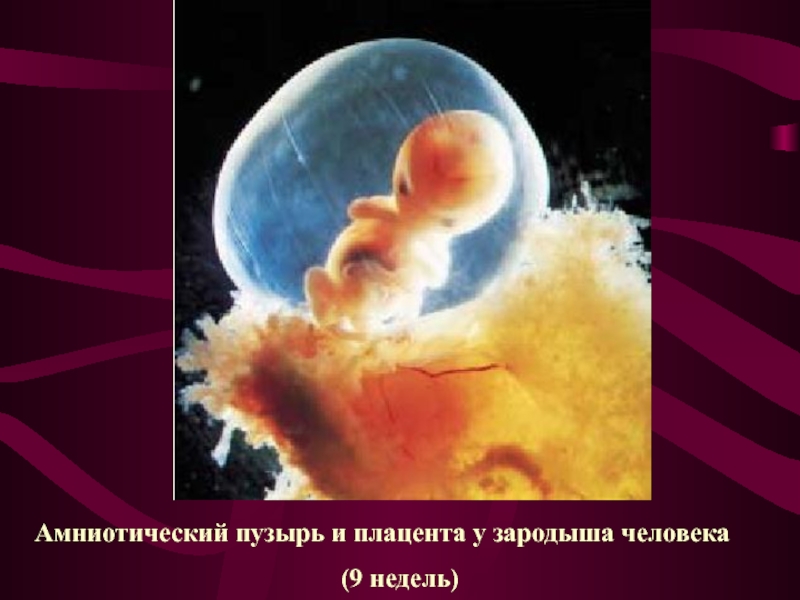

Околоплодный пузырь и плацента: структура и функции